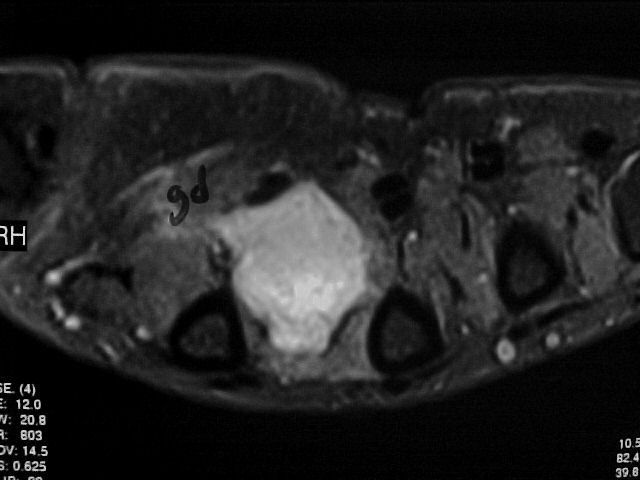

36y, male, Discrete pain and increase of volume between the 2nd and 3rd MCs

Case to follow the sent by Kyung, showing a glomus tumor in an unusual place

Glomus tumors